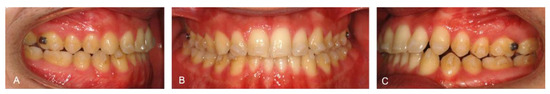

The patient correctly wore the aligners for 22 h a day with class III elastics anchored on the upper first molars and lower canines. After 12 months of treatment, the patient had improved tooth class, a positive anterior overjet, resolution of the posterior crossbite, and improved upper and lower alignment. At the end of the first phase of treatment (Figure 5), slight refinement was required. A few months later, the patient consolidated the molar and canine class I relationship, achieved a positive overjet and overbite, and resolved midline misalignment (Figure 6). At the end of the refinement phase, the patient was required to wear a long-term upper and lower Essix retention device during the night. Due to the transverse discrepancy between the upper and lower arch caused by class III malocclusion, to maintain adequate periodontal health of the upper posterior sectors, it was preferred not to expand the upper arch excessively and therefore not to resolve the crossbite of the second molars. From a cephalometric point of view (Figure 7 and Table 2), the inclination of the lower incisors and interincisal angle improved, which resulted in an aesthetic and functional enhancement. Pre-post-cephalometric evaluation, made with Deltadent® software (Outside format, Pandino, Italy), is reported in Table 3 and cephalometric tracing superimposition is shown in Figure 8.

Figure 5. Intra-oral pictures of the patient after the first treatment phase: Right lateral occlusion (A); Frontal occlusion (B); Left lateral occlusion (C).